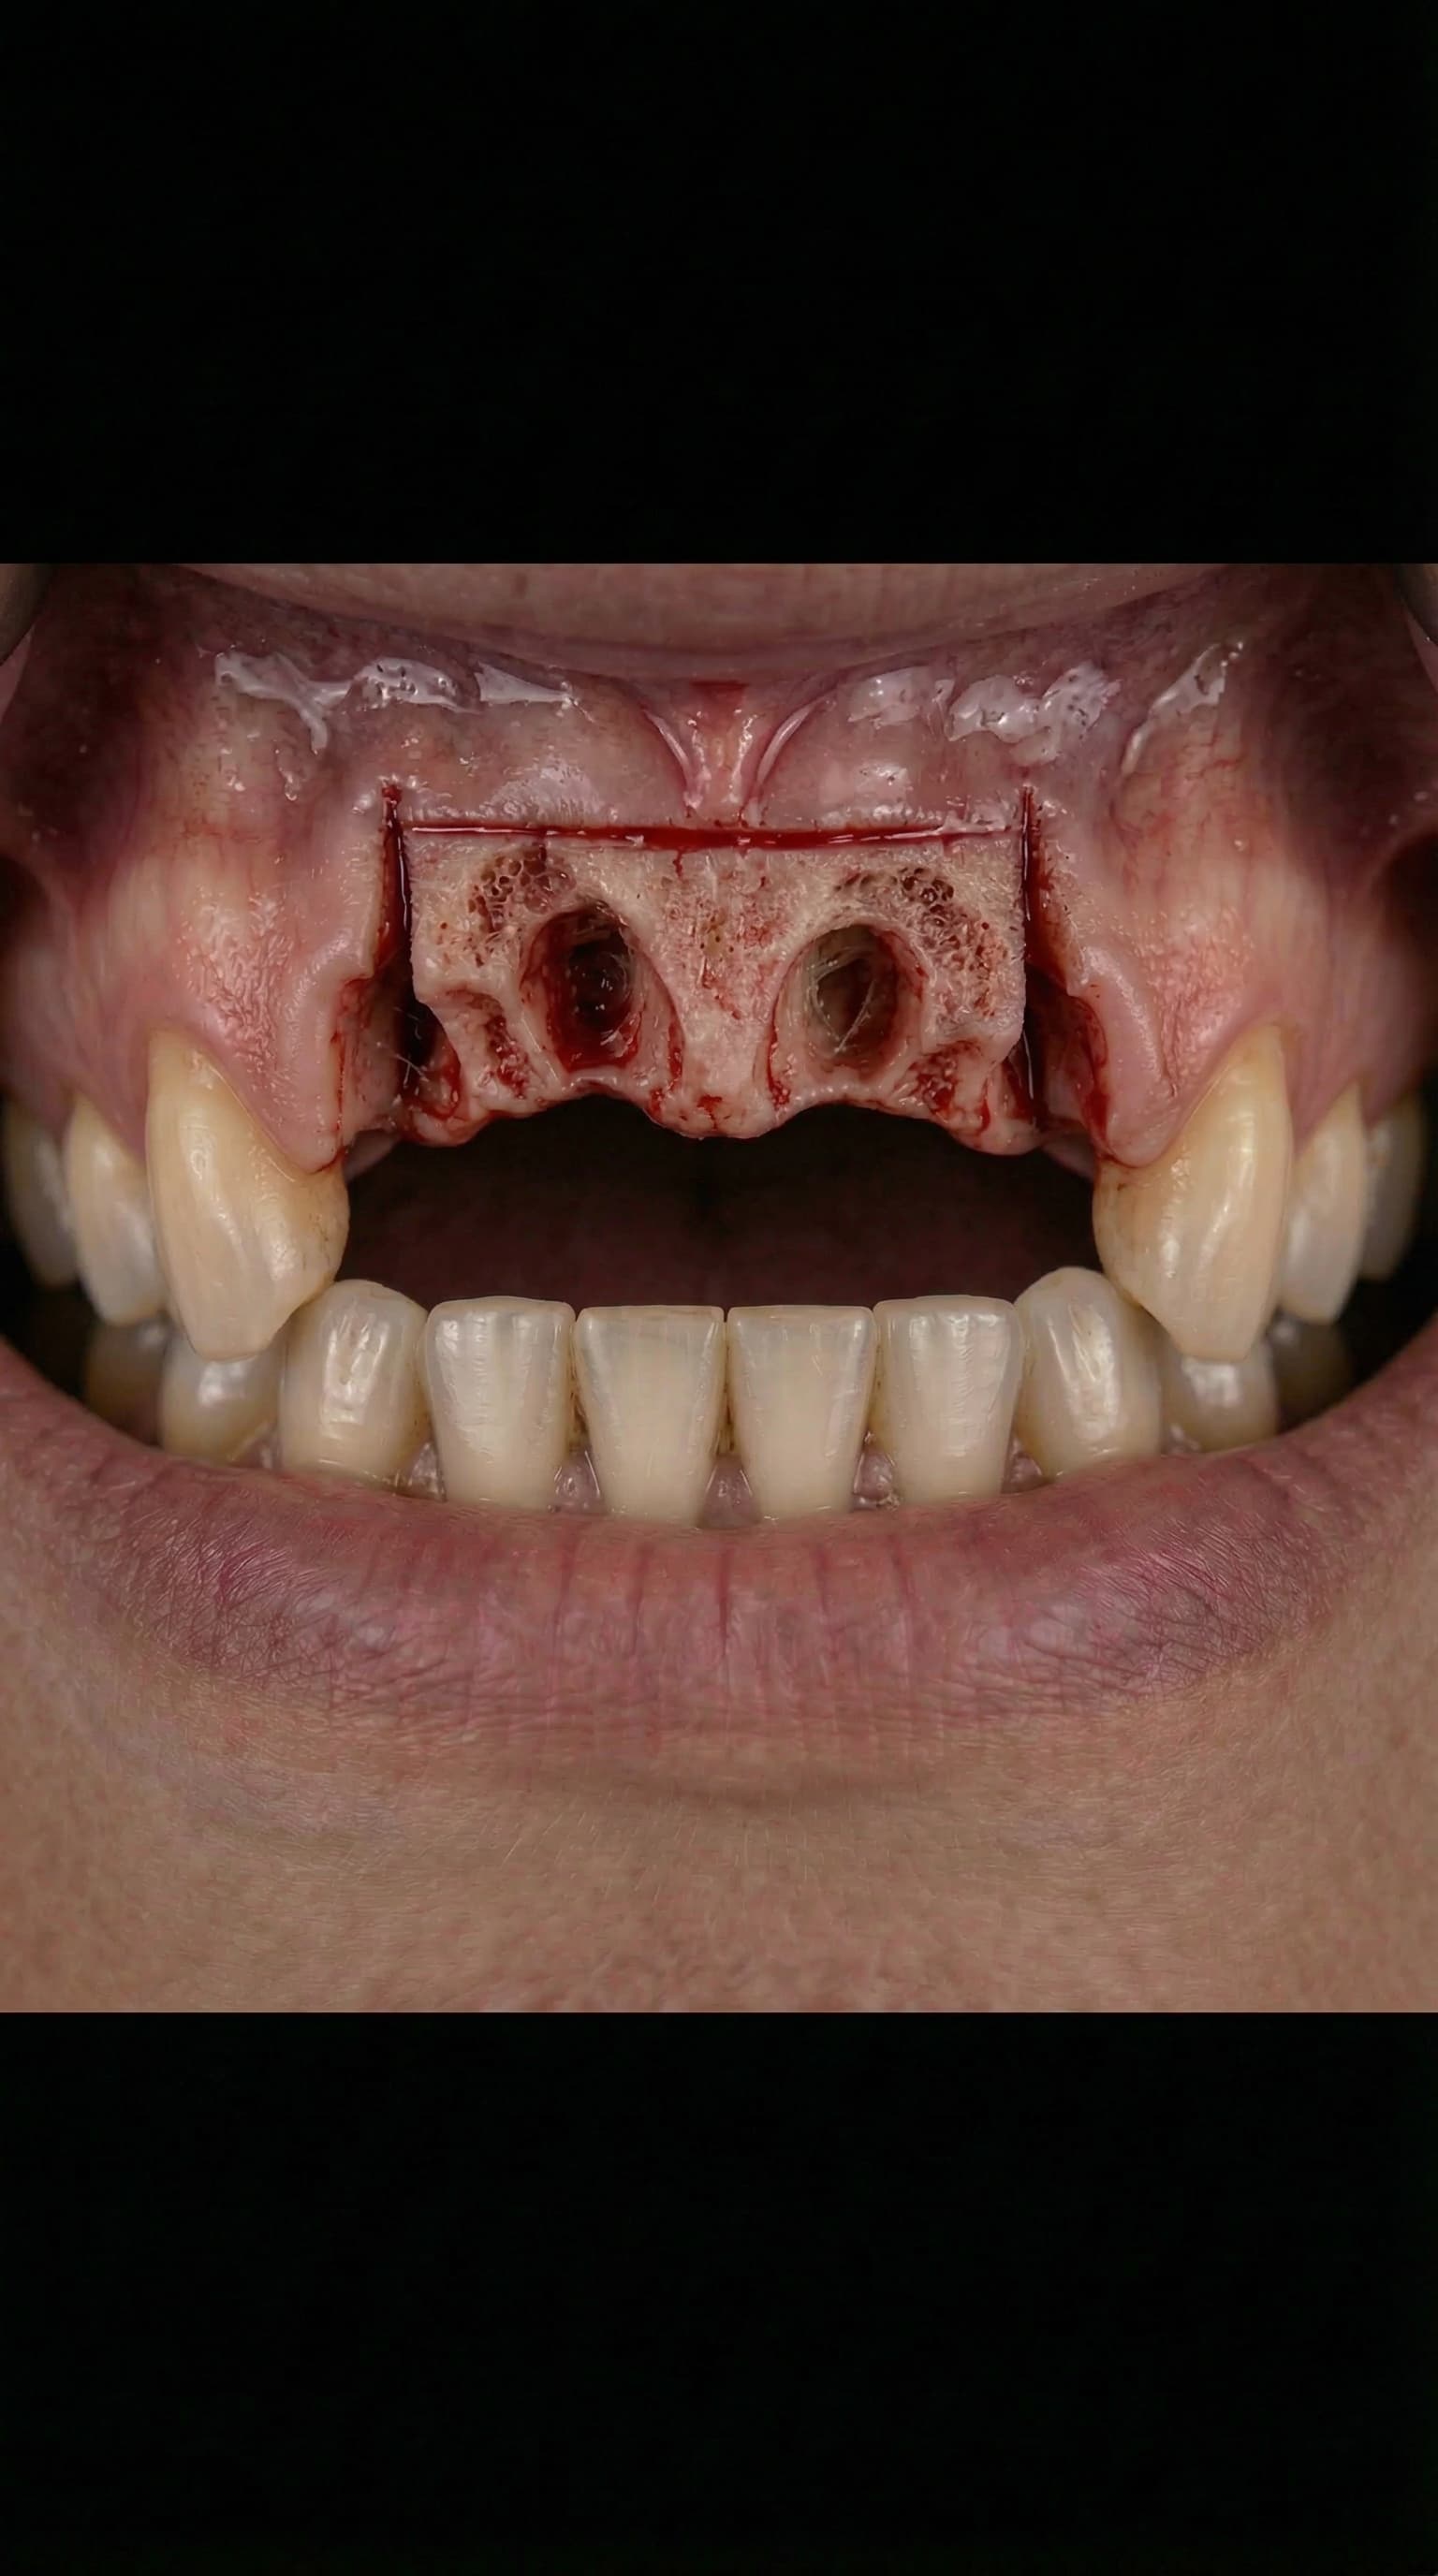

Extraction Socket

The Dental Implant Journey — from extraction to your new permanent smile

Receive a complete set of permanent teeth in a single visit with our All-on-4 and All-on-6 immediate-load implant protocols. Dr. Antipov uses 3D cone beam CT imaging and computer-guided surgical templates for precise, predictable placement — even for patients who have been told they don't have enough bone. For severe upper jaw bone loss, we offer zygomatic implants anchored to the cheekbone, eliminating the need for extensive bone grafting. Every full arch case includes same-day temporary teeth so you never leave without a smile.

Severely worn and damaged upper teeth — patient unable to eat or smile comfortably